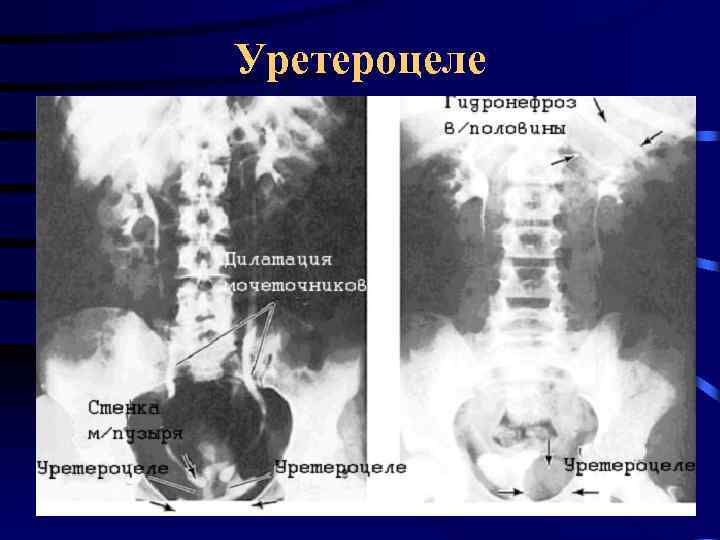

Уретероцеле

Уретероцеле